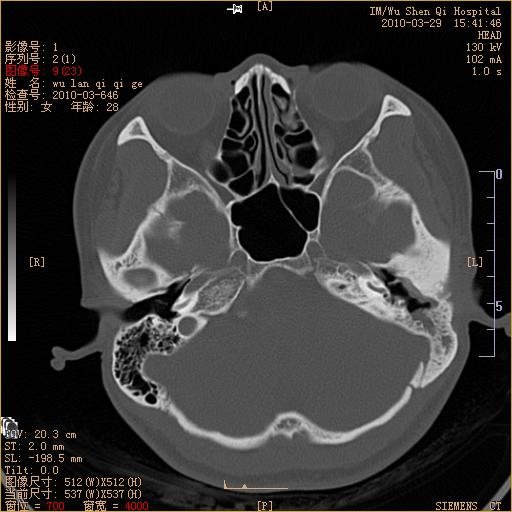

标题: CT25398:女,左耳流脓两年余,带有异物 [打印本页]

标题: CT25398:女,左耳流脓两年余,带有异物

左侧中耳乳突炎,不排除胆脂瘤形成。

左侧中耳乳突炎,胆脂瘤形成。

1)左侧慢性中耳乳突炎并肉芽肿(或胆脂瘤)形成。2)考虑左侧颞骨慢性炎症伴骨质增生硬化,不排除骨纤。